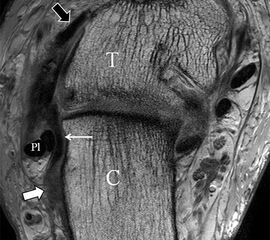

Das Ligamentum tibiofibulare posterius (hintere Syndesmose) verläuft flacher und geht nach kranial in das Ligamentum tibiofibulare interosseus und nach kaudal in das Ligamentum intermalleolare posterius über. Letzteres bildet ein artikuläres Labrum zwischen Trochlea und Talus 9.

Da also die hintere Syndesmose an der posterioren Tibia inseriert, entspricht eine Fraktur oder Infraktion des hinteren Volkmann`schen Dreiecks funktionell einem knöchernen Ausriss des Ligamentum tibiofibulare posterius (Abb. 18 a und b). Aufgrund der Koinzidenz von Syndesmosenläsionen mit Innenbandverletzungen ist bei der Beurteilung gesondert auf solche zu achten.

b. T2 fs axial. Infraktion des hinteren Volkmann‘schen Dreiecks (schmale, weiße Pfeile). Hier inserierende, intakte, hintere Syndesmose (breite, weiße Pfeile).

Abbildung 18b